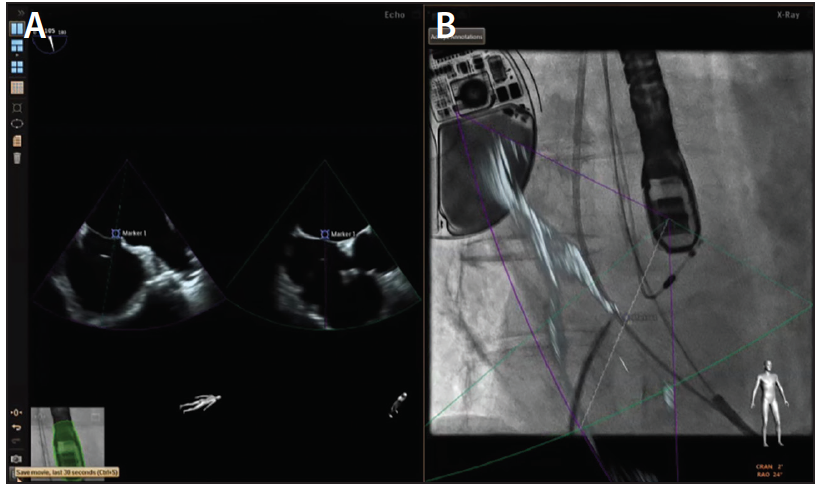

Echocardiographic-Fluoroscopic Fusion Imaging

Due to the complex 3D nature of the LAA, the implanter is essentially required to perform real-time 3D mental integration of fluoroscopic and echocardiographic data while incorporating tactile feedback to successfully execute LAAO. This has led to the development and use of echocardiographic-fluoroscopic fusion imaging technology.40 The EchoNavigator platform (Philips) allows real-time TEE-fluoroscopic coregistration, thereby empowering the interventionalist to execute precise catheter and device manipulations while visualizing cardiac soft tissue anatomy—identifying important landmarks (depicted by fiducial markers) and assessing color flow Doppler information. Using fusion imaging, the target TSP location can be tagged by placing a fiducial marker, which allows the interventionalist to precisely perform the puncture and access the left atrium (Figure 6). Fiducial markers can also be placed at the ostia of the LAA and left superior pulmonary vein. The selected TSP location, when coupled with an appropriately shaped Watchman guiding catheter, allows successful cannulation of the LAA. With the guiding catheter in the left atrium, real-time 2D echocardiographic superimposition over fluoroscopy allows the interventionalist to visualize the normally invisible cardiac soft tissue structures, enabling precise hand-eye coordination and engagement of the LAA. Coregistration also permits advancement of a pigtail catheter into the appropriate lobe of the LAA to the desired depth, which in turn allows advancement of the guiding catheter over the pigtail catheter into the LAA (Figure 7). These steps are crucial when deploying the appropriately sized device at a depth that ensures stable anchoring and a complete seal. Additional technologies such as CT-fluoroscopic fusion are also being actively developed and investigated.

Figure 7. Real-time 2D echocardiogram (A) overlaid on fluoroscopic anteroposterior imaging (B) allows engagement of the LAA using the Watchman guiding catheter.